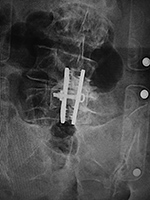

| 85 year-old woman. These images show respectively an AP radiograph of an ILIF at L4-5, an axial CT image of the ILIF, and two coronal reformatted CT images of the ILIF. There is a donar bone plug held in place by the interspinous fixation plate (clamp). |